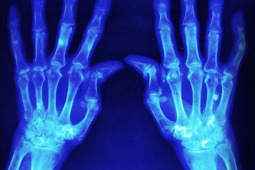

Badanie przeprowadzone przez Backera i wsp. miało na celu zbadanie zależności między obrazem MR u chorych na RZS, a oceną wyników leczenia raportowaną przez chorego (ang. patient reported outcomes, PRO’s). Wykonano analizę post hoc na podstawie danych z badania GO-BEFORE. U 291 chorych z rozpoznaniem RZS wykonywano badanie MR, w którym oceniano obrzęk błony maziowej, obrzęk szpiku oraz obecność nadżerek. Oceny aktywności choroby dokonywano w 0, 12, 24 i 52 tygodniu leczenia.

Bardziej nasilone zmiany zapalne błony maziowej, obrzęk szpiku kostnego czy obecność nadżerek kostnych były związane z wyższą wartością HAQ. Odnotowano istotną korelacja typowych dla RZS nieprawidłowości w badaniu MR z nasileniem bólu oraz globalną oceną aktywności choroby według pacjenta w 24 i 52 tyg. leczenia.

Związek między zapaleniem błony maziowej a oceną raportowaną przez pacjenta (ból, globalna ocena, stan czynnościowy) był niezależny od innych klinicznych parametrów aktywności choroby. Czym mniejszą poprawę w ocenie zapalenia błony maziowej obserwowano w toku leczenia oraz czym większa była progresja nadżerek kostnych w 52. tygodniu badania tym gorsze były wyniki leczenia raportowane przez pacjenta.